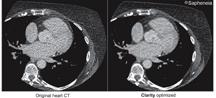

September 28, 2010 – Three new customers have joined a growing list of hospitals, imaging centers and clinics that use the Clarity CT solution to enable material reductions in the medical radiation exposed to patients. They are: Watson Clinic of Lakeland, Fla.; Zilkha Radiology of East Islip, N.Y., and Inova Alexandria Hospital of Alexandria, Va. Each of these facilities licensed Clarity CT to reduce the effective dose on CT exams across a variety of different makes and models of CT scanners.